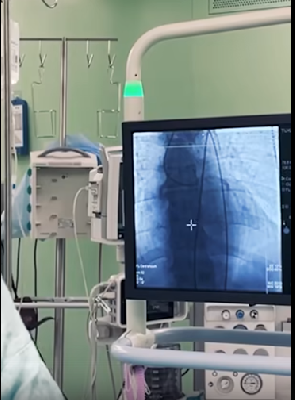

Мужчине экстренно провели обследования. КТ показало врачам уникальную картину, которую они увидели впервые в своей практике: пуля мигрировала от места ранения по верхней и нижней полым венам и остановилась в правой почечной вене.

Чтобы спасти жизнь пациента, бригада сосудистых и рентген-эндоваскулярных хирургов начала операцию:

- ювелирно выделили почечную вену и артерию

- пережали сосуды почки, чтобы извлечь глубоко расположенную пулю:

на это у врачей было всего несколько минут

- пулю извлекли за рекордные 6 минут - это было крайне важно, чтобы не допустить отмирание почки